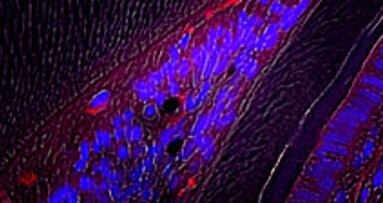

La distrazione ossea rappresenta un'elevazione localizzata del bordo alveolare tramite lo spostamento controllato di un segmento d'osso alveolare gradualmente mobilitato secondo i principi di Ilizarov: l'osteogenesi per via della sollecitazione in trazione. Nel caso della DA si tratta di una distrazione monofocale.

La tecnica chirurgica di distrazione ossea fa parte di quelle di chirurgia avanzata. Il dentista deve conoscere alla perfezione le tecniche di incisione dei lembi, quelle di osteotomia e di inserimento delle viti e placche d'osteosintesi. L’analgesia è solo locale. L'approccio si fa per via vestibolare realizzando una prima incisione al di sopra della linea mucogengivale. Lo scollamento del lembo è di tutto spessore. Il distrattore viene posizionato sulla zona ossea così esposta. L'osteotomia si fa fino alla corticale palatale. L'ausilio della piezochirurgia elimina il rischio di lesione della mucosa palatale o linguale. Il blocco osseo è mobilitato con uno scalpello e il distrattore fissato con viti di osteosintesi di 5 mm. La parte fissa è bloccata sulla base più apicale rispetto alla linea di osteotomia e la parte mobile del distrattore fissata sulla porzione da mobilizzare. Si procede alla verifica del buon posizionamento della DA attivandola un po' e riposizionandola come dapprima. L'intervento viene completato con suture senza nessuna trazione sui tessuti.

Due pubblicazioni che hanno trattato più di 300 casi (Chin et Hiding) hanno dimostrato un aumento dell'altezza dell'osso pari al 95% dei casi e una perdita di impianti inferiori al 2% dopo 6 anni. I vantaggi della tecnica sono: l'espansione simultanea dell'osso e dei tessuti molli, l'assenza di sito donatore per l'osso; l'intervento si realizza in analgesia locale e si minimizza il tempo per l'implantologia rispetto alle procedure classiche di RTG e ROG. Gli inconvenienti sono invece il costo, innanzitutto: 700 euro per il solo distrattore, la necessità di un secondo intervento per togliere il dispositivo. Inoltre una chirurgia non facile che necessita di un apprendimento specifico. In conclusione: la distrazione alveolare è una tecnica di chirurgia preimplantare avanzata che trova le sue indicazioni tra tutte le altre tecniche. Rappresenta un'alternativa molto interessante ad altre tecniche. Occorre un notevolissimo apprendimento: la piezochirurgia ne facilita l'esecuzione sul piano delle potenziali lesioni tessutali.